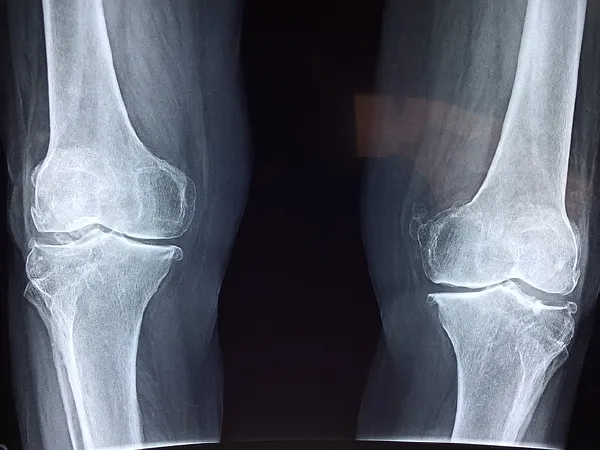

影像学检查对于确诊膝关节炎具有重要意义。X线检查是最常用的影像学检查手段,能够清晰显示关节的骨质结构、关节间隙及骨赘等变化。对于疑难病例,还可以进行磁共振成像(MRI)或超声检查,以进一步评估关节软骨、滑膜及周围软组织的情况。

目前,临床上常用的膝关节炎分期标准主要基于影像学检查结果。其中,Kellgren-Lawrence分级法是最常用的标准之一,将膝关节炎分为四个等级:0级无明显改变,1级轻微关节间隙变窄及骨赘形成,2级关节间隙明显变窄及中度骨赘形成,3级大量骨赘形成及骨端硬化,4级关节间隙消失及重度骨质改变。此外,还有一些其他的分期标准,如Osteoarthritis Research Society International(OARSI)分级系统等。